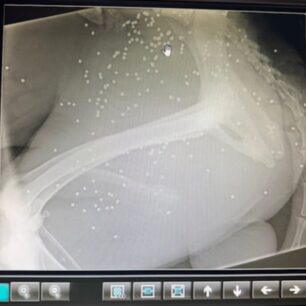

Στις 3 Οκτωβρίου φιλόζωοι εντόπισαν ένα από τα ελάχιστα σκυλιά που έχουν επιζήσει στο Κρυονέρι Αιτωλοακαρνανίας πυροβολημένο. Η αρχική εντύπωση του κτηνιάτρου ήταν ότι το σκυλί έχει δαγκωθεί από άλλο ζώο εντούτοις η ακτινογραφία έδειξε τι έχει συμβεί. Το σώμα του είναι γεμάτο σκάγια…

Ο Περσέας βρέθηκε πυροβολημένος, με το σώμα του γεμάτο σκάγια. Ευτυχώς τραυματισμενος γύρισε στο μέρος που τον φρόντιζαν να ζητήσει βοήθεια.. Σοβαρό τραύμα, δεν  μπορεί ακόμη να σταθεί όρθιος.

Πρέπει να κάνει πλαστική στο σημείο που πυροβολήθηκε, γιατί είναι εκτεθειμένο το οστό του.